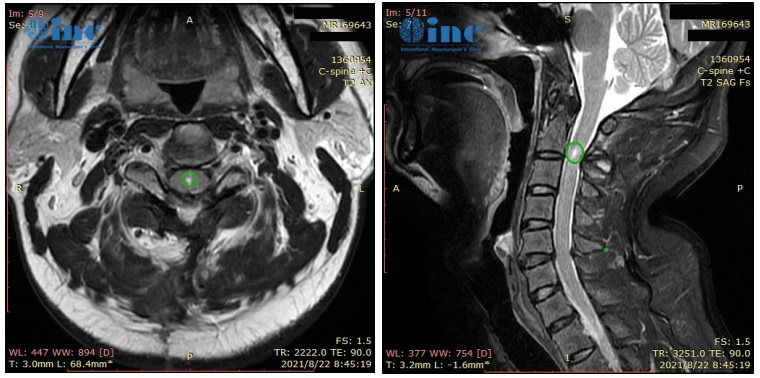

术前颈2平面脊髓内可见椭圆形短T1长T2信号,信号均匀,边界尚清,大小约7.8X4.1X5.0mm,增强后明显强化。术后肿瘤得到顺利全切,无新发神经损伤,无瘫痪,术后复查没有复发

(患者术前病变)

术后3个月随访:“8月22日的核磁共振成像看起来很棒,令人满意!肿瘤被很好地切除了。磁共振成像上只有一个很小的切除腔。此外,病理学方面,我们预估的室管膜瘤II级得到证实。我建议患者未来每年进行一次MRI检查……”这是INC国际神经外科顾问团的德国Helmut Bertalanffy(巴特朗菲)教授对刘先生术后3个月的随访回复。